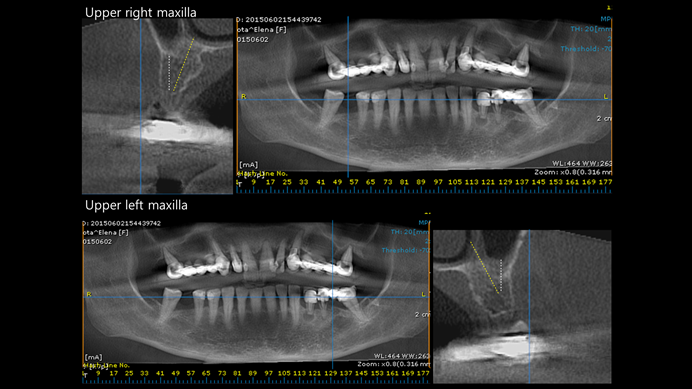

Clinical case: Extraction of all teeth in upper maxilla,

immediate implant placement, & provisionalization

- Courtesy of Dr. Iulian Filipov, Romania -

Keywords

AnyRidge, immediate placement, immediate provisionalization, maxillary fully edentulous case, initial stability, edentulous, Dr. Iulian Filipov, R2GATE, MEGA ISQ

Products:

AnyRidge implant system, Mega ISQ, R2GATE